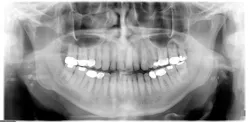

Radiographic assessment: Small, multiple, radiopaque, ill-defined, calcareous objects are seen on the radiograph (see Figure 1). The radiograph presented in this column was taken in 2015 of a 76-year-old male.

These opacities are not limited to the palatine tonsils but may also be seen in accessory lymphoid tissue. Sometimes what is referred to as "ghost images" appear on a pantomograph, making a pseudotonsillolith visible on the opposite side. This occurs because the object is located between the X-ray source and the center of rotation of the cassette. The patient may have oral calcifications bilaterally or unilaterally, so further evaluation is always needed.